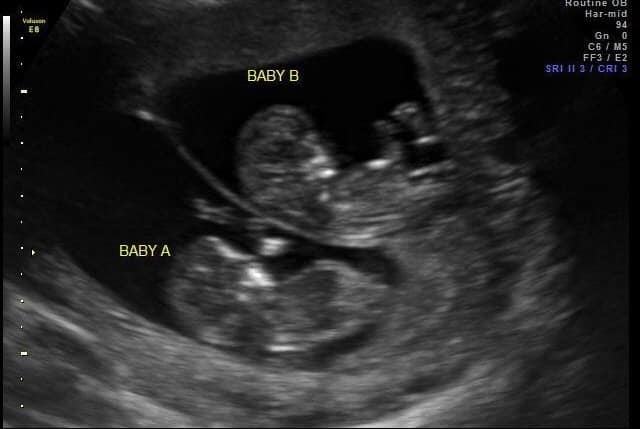

Ultrasound Photos at 12 Weeks Pregnant With Twins